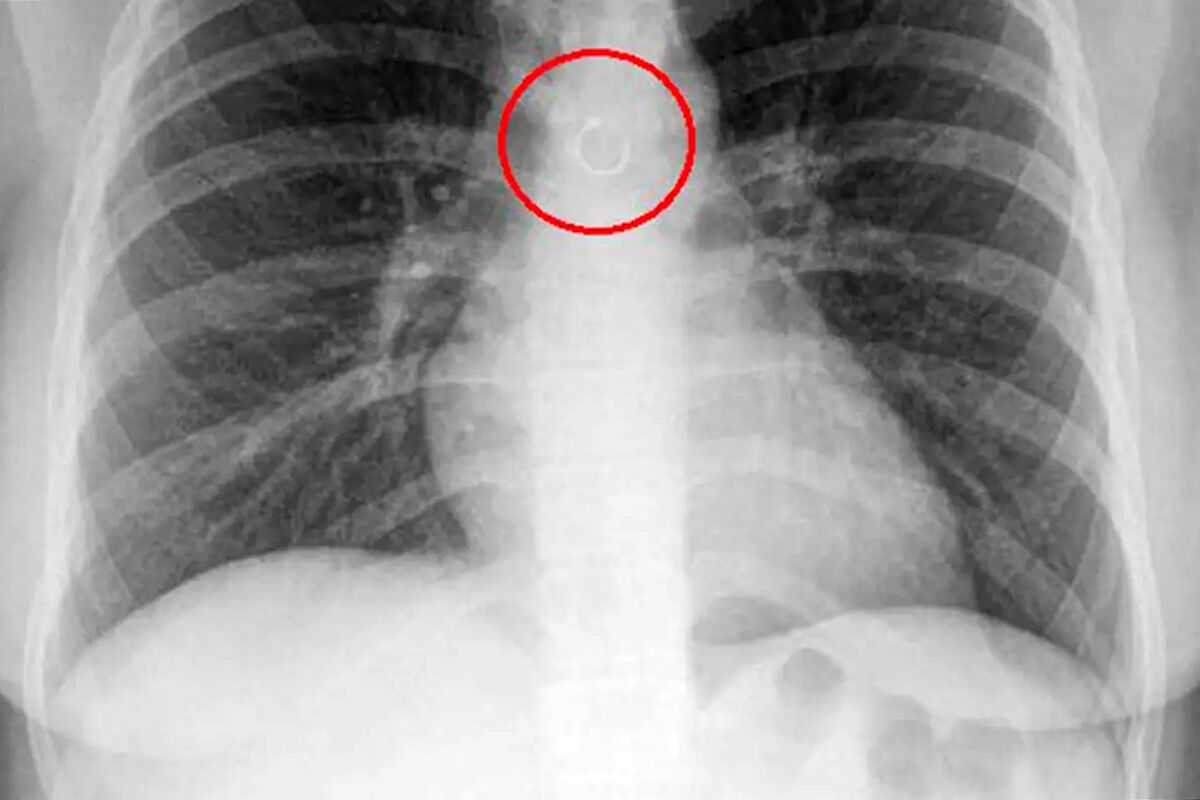

Женщина обнаружила, что потерянное кольцо в носу попало в ее легкие

Fox News: мексиканка случайно проглотила кольцо из носа, которое попало в легкие

В Мексике женщина обнаружила, что потерянное кольцо в носу попало в ее легкие, пишет Fox News.

Во время обследования выяснилось, что украшение из пирсинга в носу каким-то образом оказалось глубоко в дыхательных путях девушки и застряло в легких. Металлический элемент находился всего в полумиллиметре от аорты, что могло привести к опасным последствиям, добавили медики.

Первая операция, которая должна была занять около 20 минут, затянулась более чем на час. Врачи не смогли сразу извлечь предмет, поскольку он уже начал прикрепляться к внутренним тканям.

Из-за высокого риска кровотечения девушке Монике потребовалось повторное, более сложное хирургическое вмешательство. По ее словам, перед операцией она даже написала прощальное письмо близким, опасаясь худшего исхода.